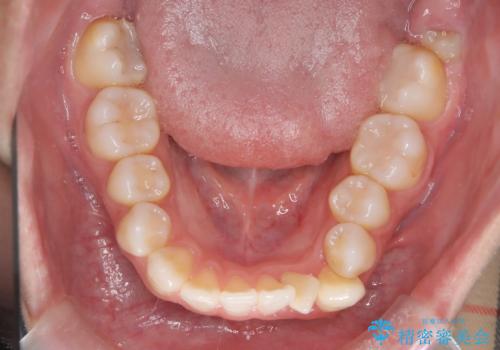

- 治療計画

上下左右の第一小臼歯を抜歯し、クリアブラケット(白い装置)とメタルワイヤーを使用して矯正を開始。初期には犬歯のアーチ内への整列を優先し、中盤からは前歯と奥歯の咬合関係の調整を進めました。審美性に優れた装置を使用したことで、治療中も目立ちにくく、見た目へのストレスが少ない点も評価されています。全体の治療は1年半で完了し、見た目・噛み合わせともに大きく改善。患者本人も「短期間でここまで変わるとは思わなかった」と満足されていました。